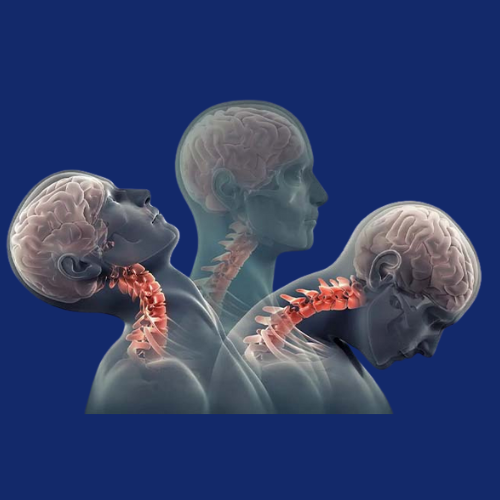

The cervical spine, located in the neck region, plays a crucial role in supporting the head and enabling motion. However, it is also prone...Read More

The cranio-vertebral junction (CVJ) is a complex anatomical region at the junction of the skull and upper cervical spine (C1–C2), responsible for supporting...Read More